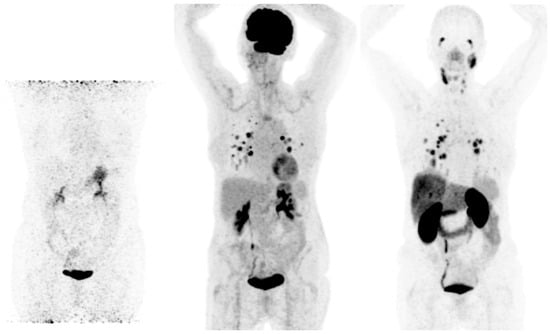

- Fu, H.; Fu, J.; Huang, J.; Pang, Y.; Chen, H. 68Ga-FAPI PET/CT Versus 18F-FDG PET/CT for Detecting Metastatic Lesions in a Case of Radioiodine-Refractory Differentiated Thyroid Cancer. Clin. Nucl. Med. 2021, 46, 940–942. [Google Scholar] [CrossRef] [PubMed]